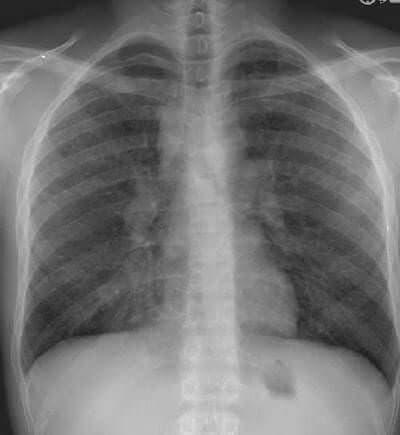

Belirtileri her hastada farklı olabilmektedir. Teşhis konduğunda hastaların yaklaşık üçte ikisinde herhangi bir belirti saptanmaz. Genellikle başka bir amaçla akciğer filmi çekildiğinde tesadüfen tanı konulmaktadır. Hastaların %90’ında akciğer tutulumu bulunmaktadır.

Doku biopsisi, uygun radyolojik görünüm ve hasta kliniği ile tanı konmaktadır. Bazı hastalarda tanı koymak zor olabilir.